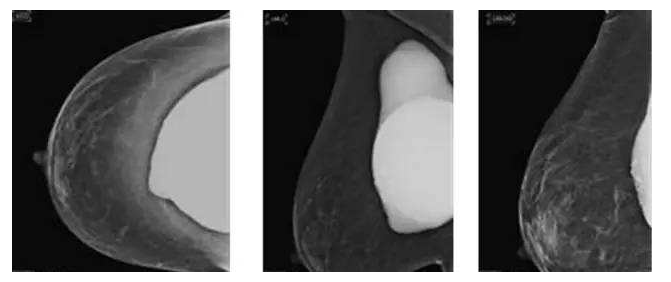

假体隆胸10年后将面临什么样的问题?

假体隆胸手术发展至今已有几十年历程,随之时代的发展,医学的进步,现代隆胸技术在不断升级,假体质量也在不断提高。现代信息的广泛传播,也让受众对于隆胸手术的了解全面化。一台成功的隆胸手术可以维持10年的时间,那么为什么是10年成为了隆胸的关键时期?10年后隆胸的人会面临怎样的问题?

置入假体在一定时间内可能出现老化现象,所以专家建议平均8-12年更换一次假体为宜,进口的硅胶假体维持时间会更长到10-20年,甚至更久。

因为假体质量不同、医生操作方式不同、个人体质存在差异,所以具体的存放时间无法被预估。所以假体隆胸10年后,应每年进行B超、核磁共振检查,以确保假体的完整性和安全性,排除并发症,如遇问题,可尽早进行处理。

假体老化最常出现的现象,比如囊壁钙化,渗漏,甚至破裂,还会随着人体组织的老化出现下垂问题。

囊壁钙化:硅胶假体在胸部存放时间过长,在硅胶和自身组织包膜之间,就有可能形成钙化沉淀。轻微的钙化不会对人体造成伤害,无需在意。但如果钙化出现较大的结块,而且集中出现在假体周围,便需要做组织取出或手术。

假体渗漏、破裂:囊膜皱褶经反复运动而老化破裂,后期渗漏或破裂,有纤维囊挛缩或急性炎症现象。假体破裂的发生率虽然很低,当假体出现明显的手感变化,形态的变化,那么这个时候就可能出现了假体的破裂,如果出现假体破裂就需要置换假体。

假体松弛下垂

如果出现假体隆胸变软下垂的问题可能是假体置入层次的问题,假体如果是放在胸部腺体下,它会随着自体的胸部往下垂而一起下垂,如果假体放在胸大肌下,那么就会出现腺体往下走,而假体不往下走,就有可能形成四个胸部的情况。

最后提醒大家,一般情况下假体维持10-20年基本没有问题,不必对此过于忧虑。时常观察胸部大小变化,手感软硬程度,每年做好定期检查即可。